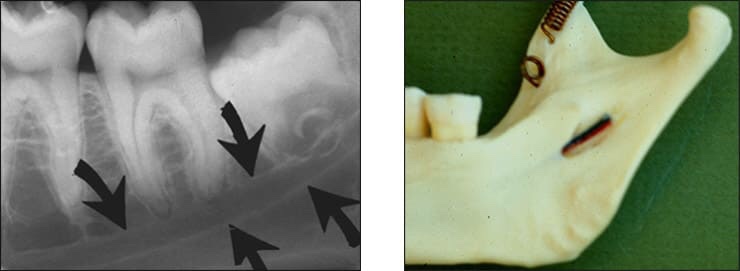

• Mental foramen – Appear as round slit like irregularity, partial or completely cortical radiolucency located in apical region of premolars.

• External oblique ridge – The external oblique ridge or line is the bony anterior border of the ramus located on the outer aspect of the mandible. This ridge has a downward diagonal course. Radiopaque.

• Internal oblique ridge – Irregular crest of bone on lingual surface of body of mandible. It runs parallel to but below the external oblique ridge. The internal oblique ridge is sometimes referred to as the mylohyoid line.

• Mandibular canal – Tube like passage through bone that travels along the length of mandible in contact with the apex of third molar.It is also referred to as the inferior alveolar nerve canal.

• Submandibular fossa – It is scooped but depressed area on bone located lingually below the myelohyoid ridge.This structure is also referred to as the submandibular gland fossa or mandibular fossa.